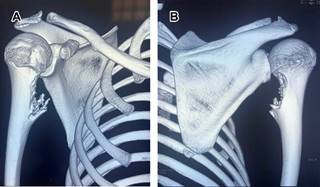

Las radiografías muestran una lesión exofítica con continuidad corticomedular con el hueso adyacente (Figura 1), con base de implantación sésil o pedunculada. La ecografía visualiza la capa cartilaginosa como un área hipoecoica sobre la corteza ósea, la tomografía computarizada (TC) permite visualización de la continuidad corticomedular de la lesión (Figura 2), la resonancia magnética (RM) es de elección para valorar las estructuras circundantes a la lesión, la capa de cartílago no mineralizada muestra señal alta en T1 y T2 (Figura 3). La resección está indicada al final del crecimiento.

Figura 2: Imágenes de tomografía computarizada en 3D en vistas coronal anterior (A) y coronal posterior (B), se observa exostosis de base ancha que semeja “estalagmitas” en su zona distal correspondiendo a osteocondroma.